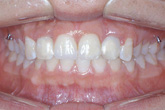

교정치료 후 debonding과 함께 상악 6전치 설측면에 .0195 twistflex를 사용한 lingual bonded retainer를 부착하였다. space closure와 함께 gingival bunching이 중절치 부위에 나타나 있음으로 충분히 기다린 후 (6개월 정도) 최종 보철물을 시행하기로 계획하였다.

최종 보철물 시행 시 필요하면 양 중절치  부위에 치은성형술 개념의 gingivectomy를 시행하고 다음과 같은 보철 치료를 계획하였다 (그림 7,8).

1) 측절치 임시보철물의 근심면을 삭제 (1mm 정도)

2) 중철치의 laminate 수복 (폭경은 1mm, 장경은 2mm 정도 증가)

3) 중철치 형태에 맞추어 측절치 최종보철 수복

그림 7. 증례환자의 교정치료 후 모습으로 차후 중절치 부위의 치은성형술과 함께, 측절치 임시보철물의 근심면 삭제 후 중절치의 라미네이트 수복(폭경은 1mm, 장경은 2mm 증가) 그리고 측절치의 최종보철로 심미적 보철물을 기대할 수 있다.